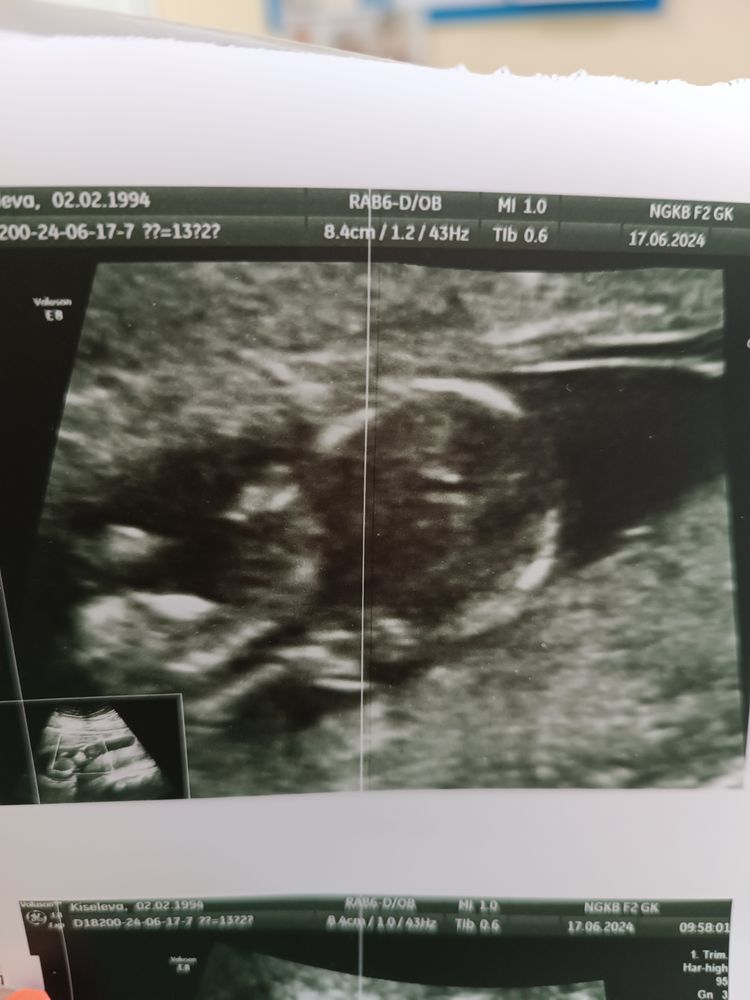

Вчера прошли свой первый скрининг с малявкой. Врач сказал все хорошо. Дал фоточку. А я сравниваю со старшим сыном и уже понимаю что копия сына и моя копия будет